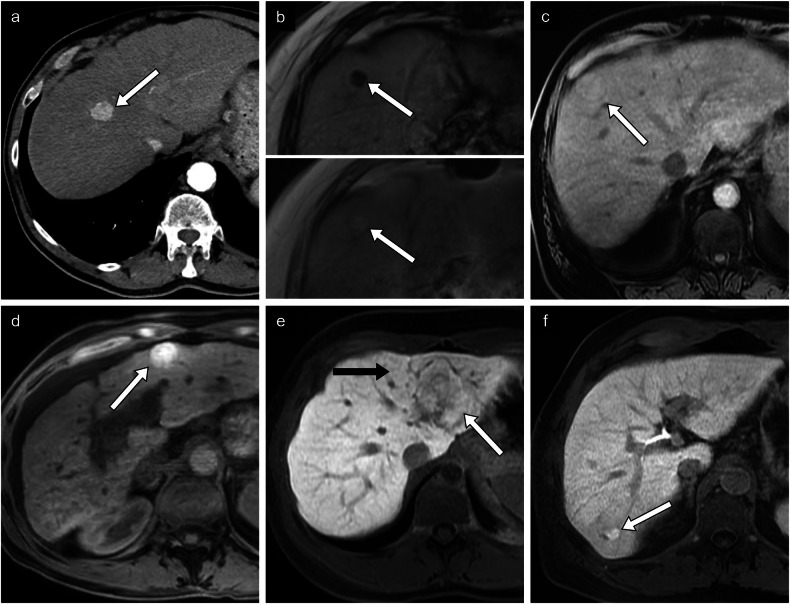

Fig. 6.

Non-proliferative prognostic imaging features. a HCC in a 73-year-old man with alcohol-associated liver disease. Axial arterial phase CT image of a small 1.8-cm lesion found in segment VIII. Histologic diagnosis was a well-differentiated HCC. b HCC in a 72-year-old man with alcohol-associated liver disease. Axial T1-weighted out-of-phase (top panel) and in-phase (bottom panel) MR images of a 1.4-cm nodule demonstrating signal loss in the out-of-phase image compatible with intralesional fat. Histologic diagnosis was a moderately differentiated steatohepatitic type HCC. c HCC in a 75-year-old man with alcohol-associated liver disease. Axial non-contrast T1-weighted MR image of an isointense lesion compared to the hepatic parenchyma in segment VIII. Histologic diagnosis was a well-differentiated HCC. d HCC in a 48-year-old woman with autoimmune cirrhosis. Axial non-contrast T1-weighted MR image of a hyperintense lesion compared to the hepatic parenchyma. No histologic diagnosis was available. e HCC in a 23-year-old woman without underlying chronic liver disease. Axial T1-weighted hepatobiliary phase MR image of 5.2-cm lesion in segment II demonstrating isointensity (white arrow) compared to the surrounding liver (black arrow). Histologic diagnosis is a well-differentiated HCC. f HCC in a 63-year-old man with chronic hepatitis C viral infection and alcohol-associated liver disease. Axial T1-weighted hepatobiliary phase MR image of a 1.5-cm hyperintense lesion in segment VI. Histologic diagnosis confirmed a moderately to poorly differentiated HCC